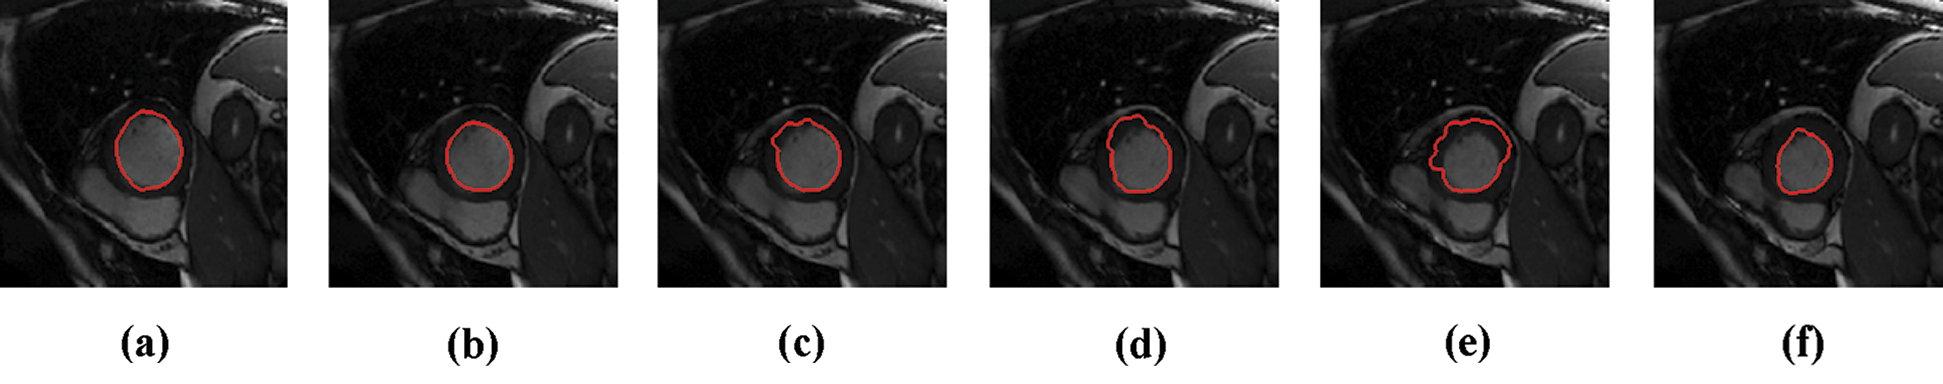

The experimental results are categorized into two distinct sections to underline both the segmentation and psoriasis lesion localization results. The presented results of this paper were obtained through using different 6 techniques to 300 sets of CVD. In this paper, multi-axis CMR database was used in three axes for 6 case studies to provide the results of various segmentation schemes. In this section, the employed techniques for studying and segmenting medical images are executed using MATLAB. Figs. 1a–1f present the Caselles segmentation technique results. These results indicate that this technique gives better results when the initialization step is suitable and the image has a high intensity gradient at the edge between the cavity and the myocardium of LV. It is also clear from the results that the blood pool segmentation depends on the boundary features. Both of Li and Bernard segmentation techniques show a wide band segmented results that are not reasonable to the blood pool segmentation as shown in Figs. 2 and 3. This is apparently visible in the Bernard segmentation technique where the segmentation partitions of each slice to bright regions and dark regions cannot separate the LV cavity from other parts of the image. The relationship between each pixel and its adjacent neighbors is considered. As it could be seen from Figs. 4a–4f, the blood pool of LV is purely delineated. That is the resulted segmented image of the Chan-Vese technique appears well-defined. Based on the obtained results, one can say Chan-Vese technique works well with homogenous regions such as cardiac images. In addition, the resulted segmented slices appear of high smoothing degree as well. The segmented images from the blood pool of LV obtained using the Lankton-Yezzi segmentation is presented in Figs. 5a–5f. As it could be seen from these figures, the quality of the segmentation process using the Lankton-Yezzi technique depends on the initialization. As it could be seen from Figs. 6a–6f, the two cycles of Shi-Karl segmentation technique produce good quality segmentation to the LV blood pool.

Figure 1: Sample results of Caselles technique